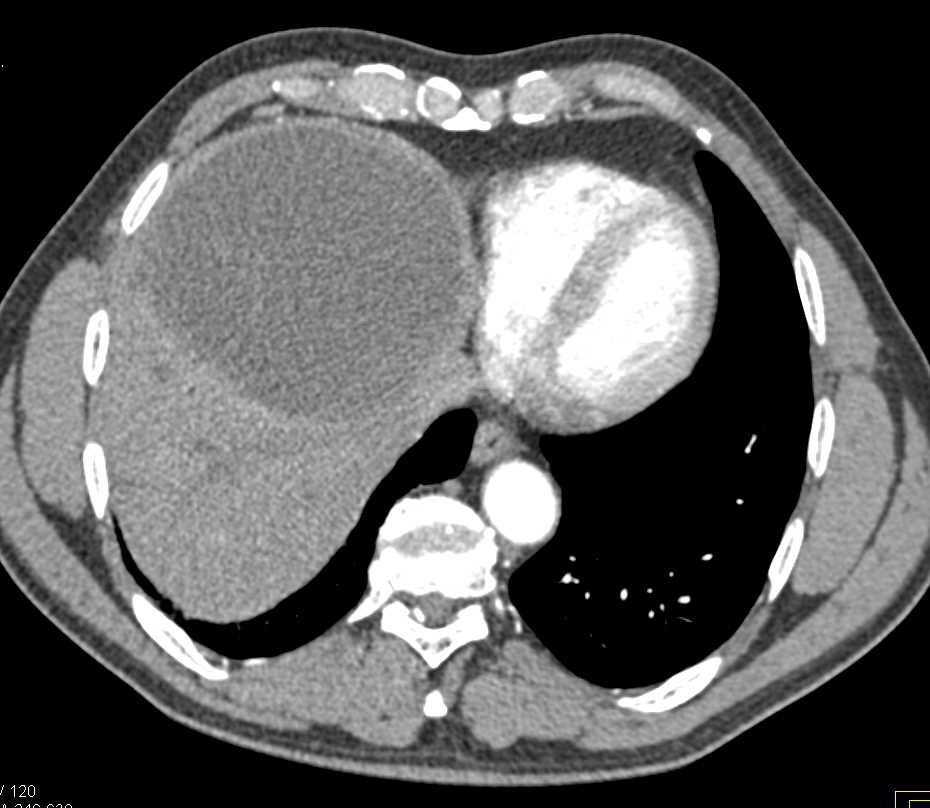

Hepatic Abscess